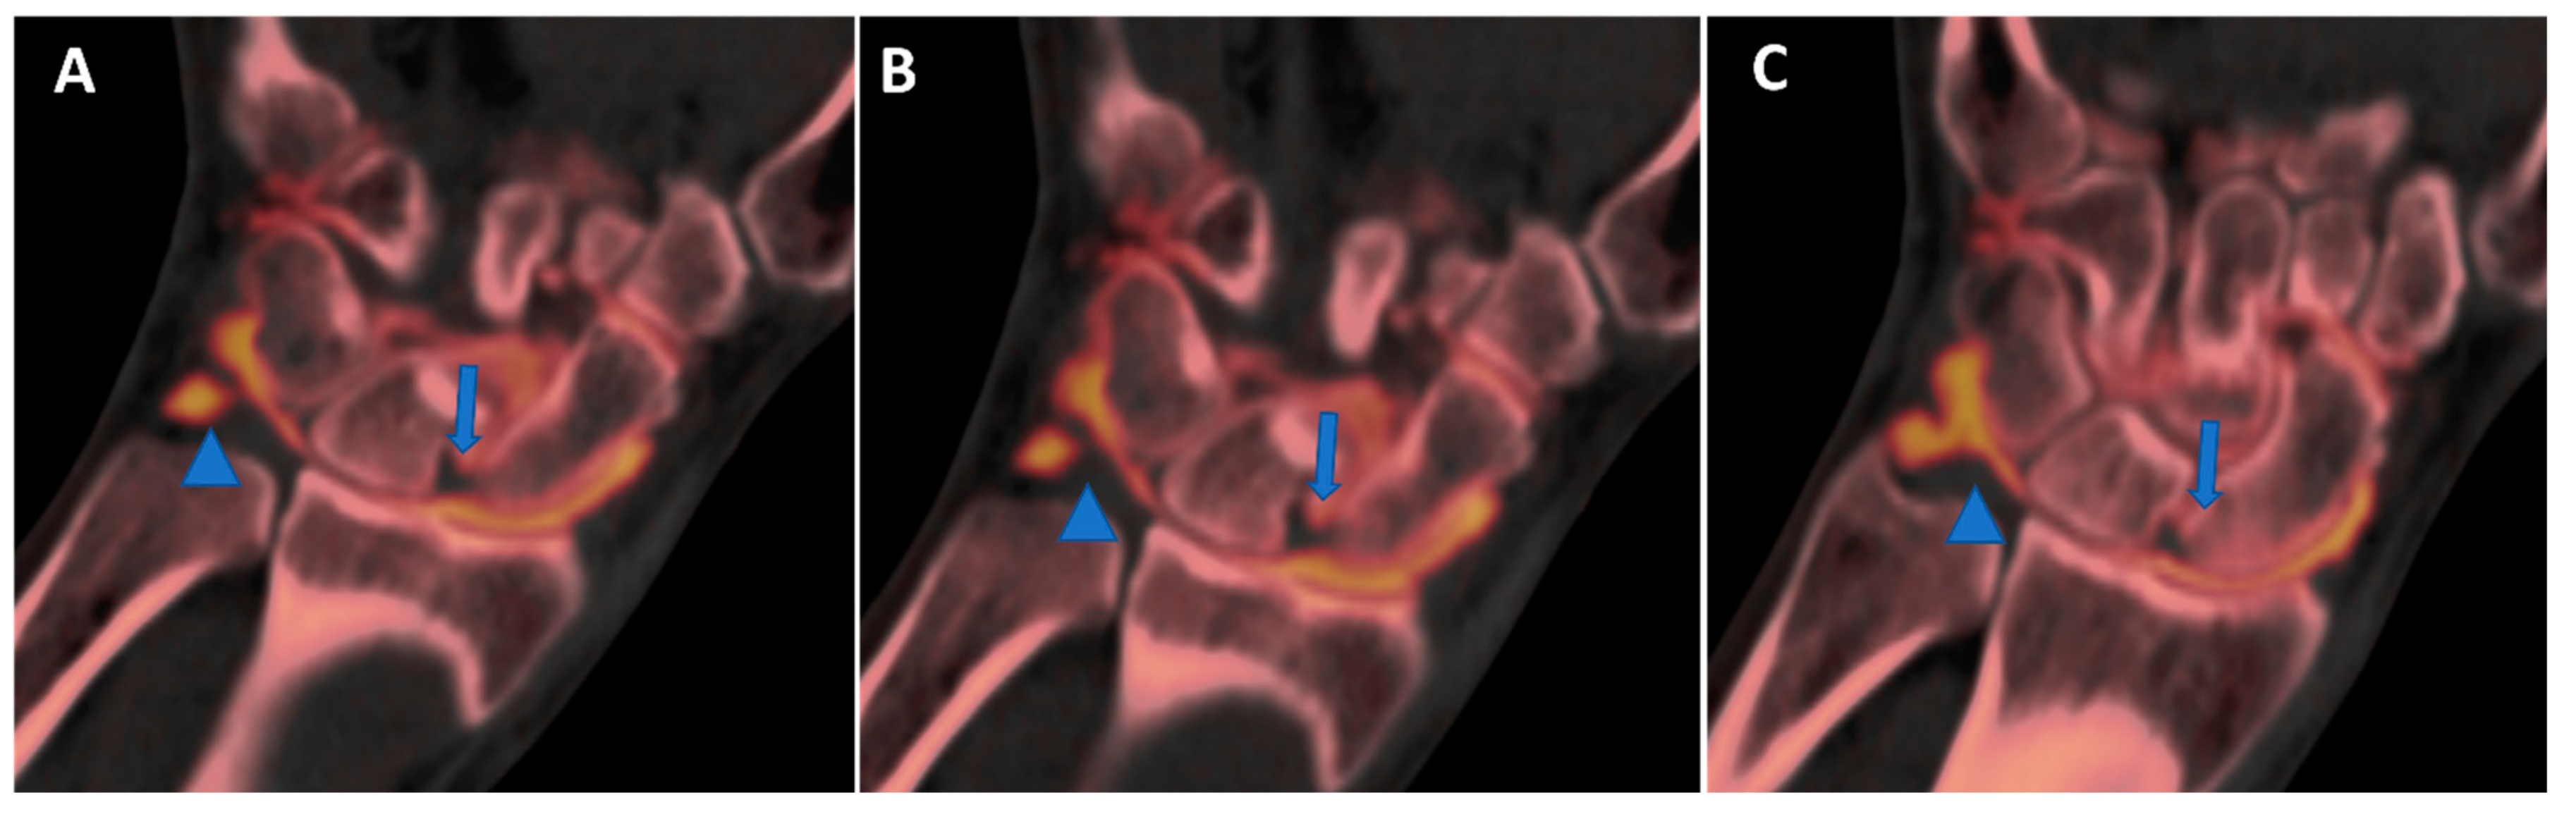

Figure 10.

High-spatial-resolution wrist anatomy using DECTA. On the 0.4 mm coronal DECTA iodine map images (A–C), a triangular fibrocartilage complex (arrowhead) and a scapho-lunate ligament (arrow) are nicely depicted.